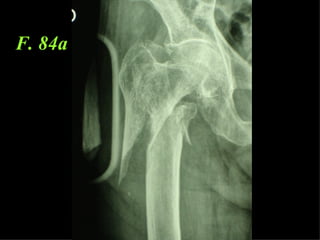

3  INSUCCESSI

F. 84a

CONCLUSIONI Perché non mettere un chiodo?  Senz’altro se il muro  laterale è fratturato  così come il punto di introduzione della  vite cefalica,perché la tecnica è più semplice

… ma  se il muro laterale è integro , la sintesi con la placca di Gotfried è  migliore e se  applicata con la  necessaria perizia tecnica garantisce  ottimi risultati.